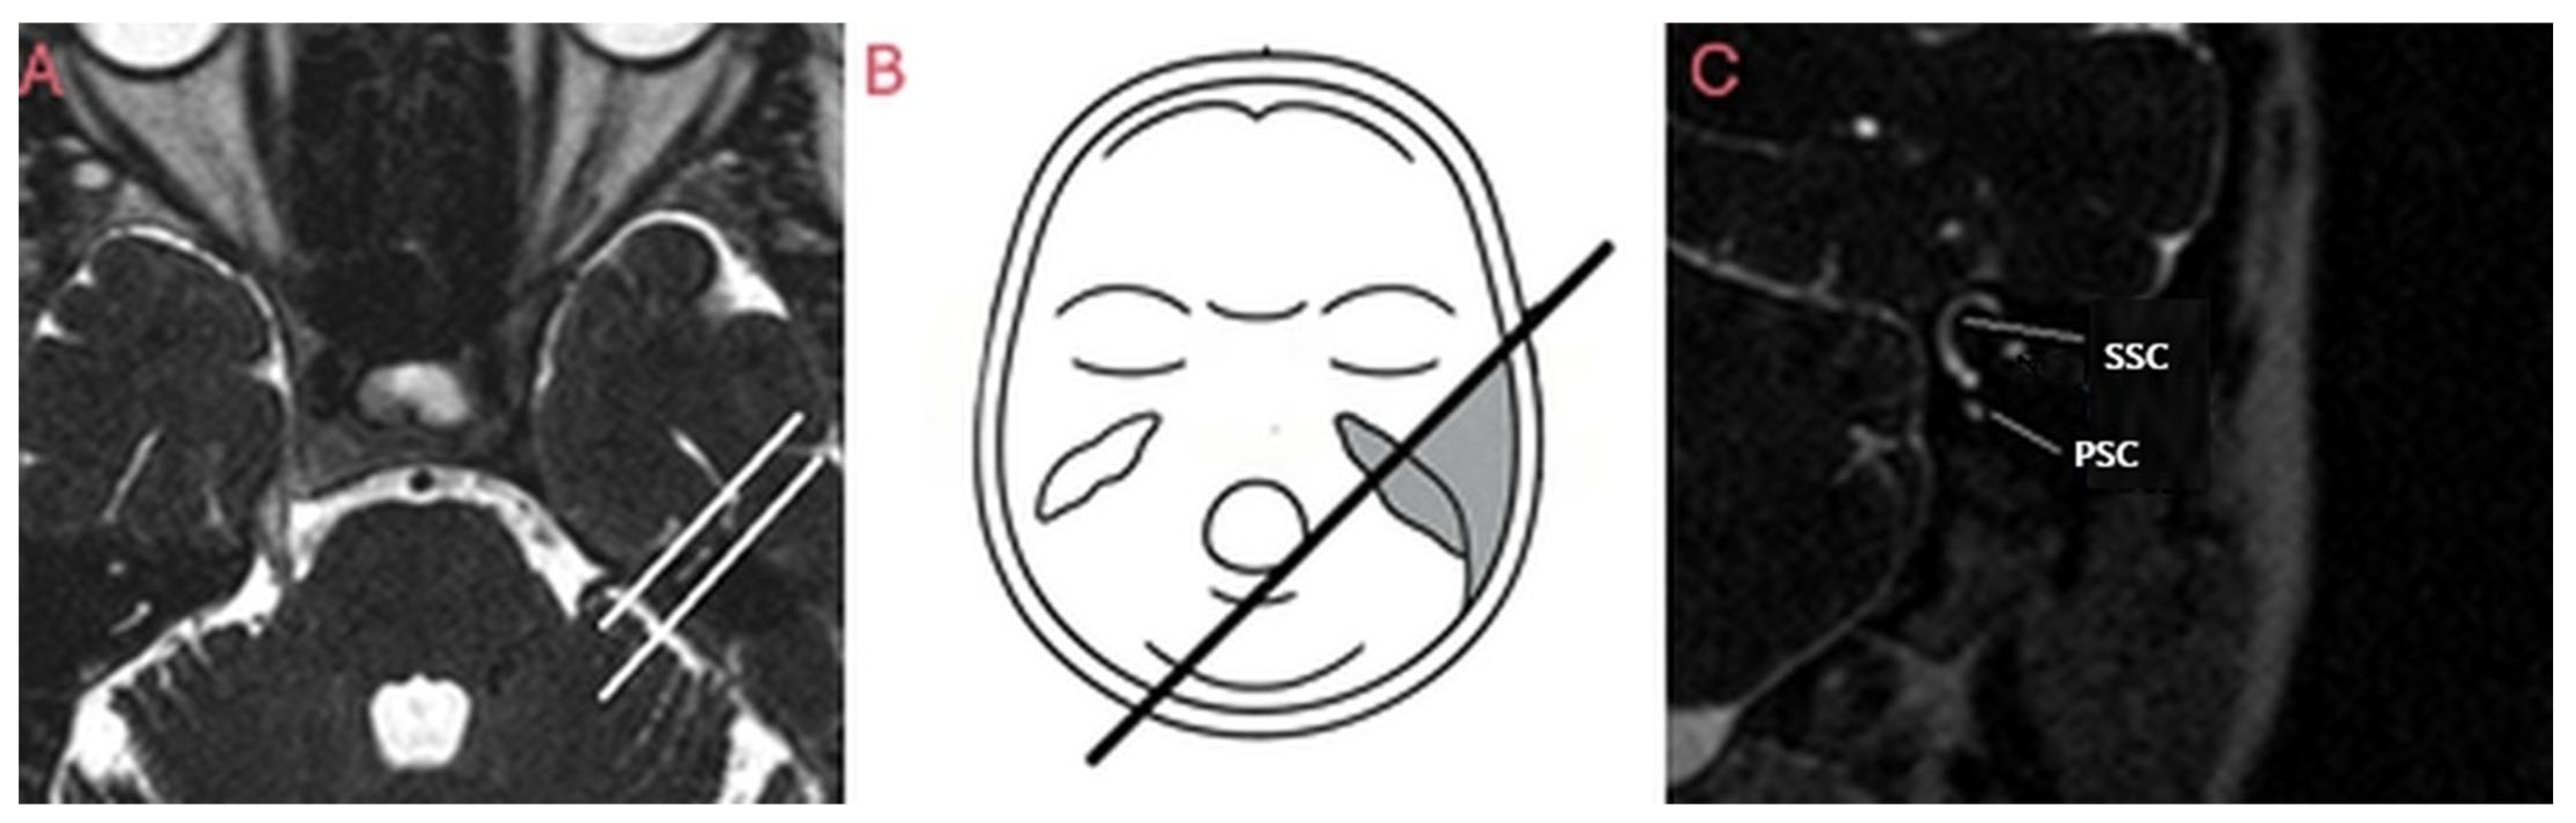

2.2. Study Procedures

2.3. Intervention Protocol or Study Groups